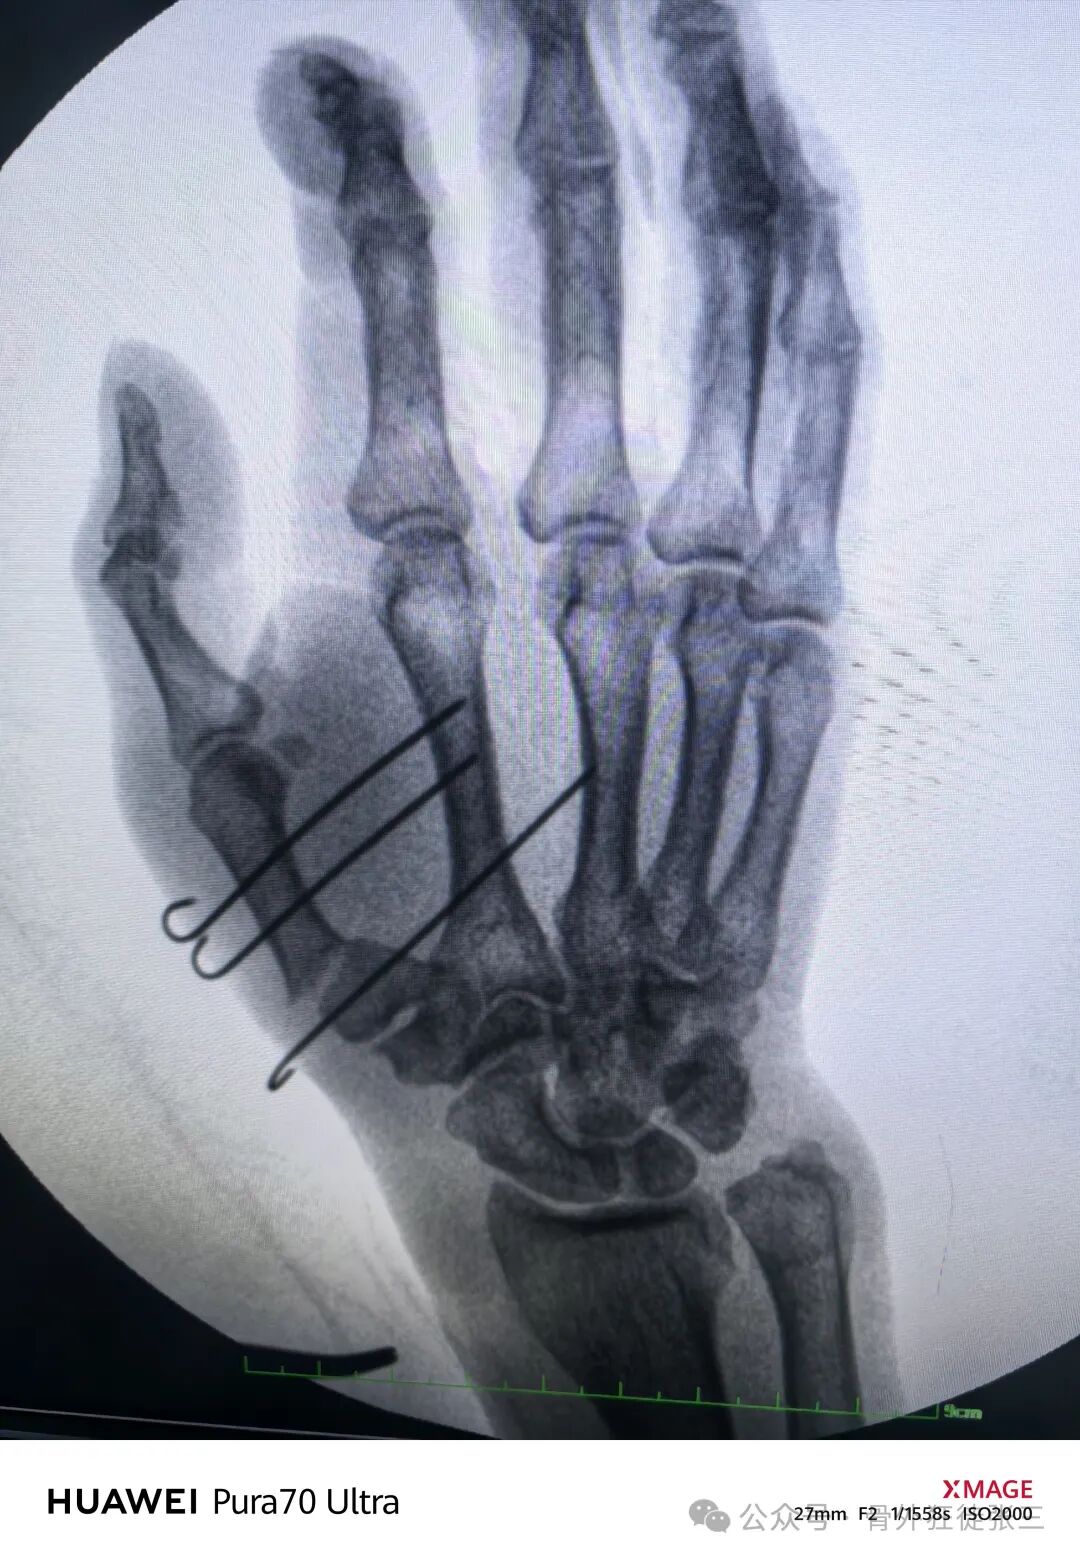

三、Wintersein骨折 (关节外骨折)

和书上固定方式几乎一样

最后再次来复习下书本